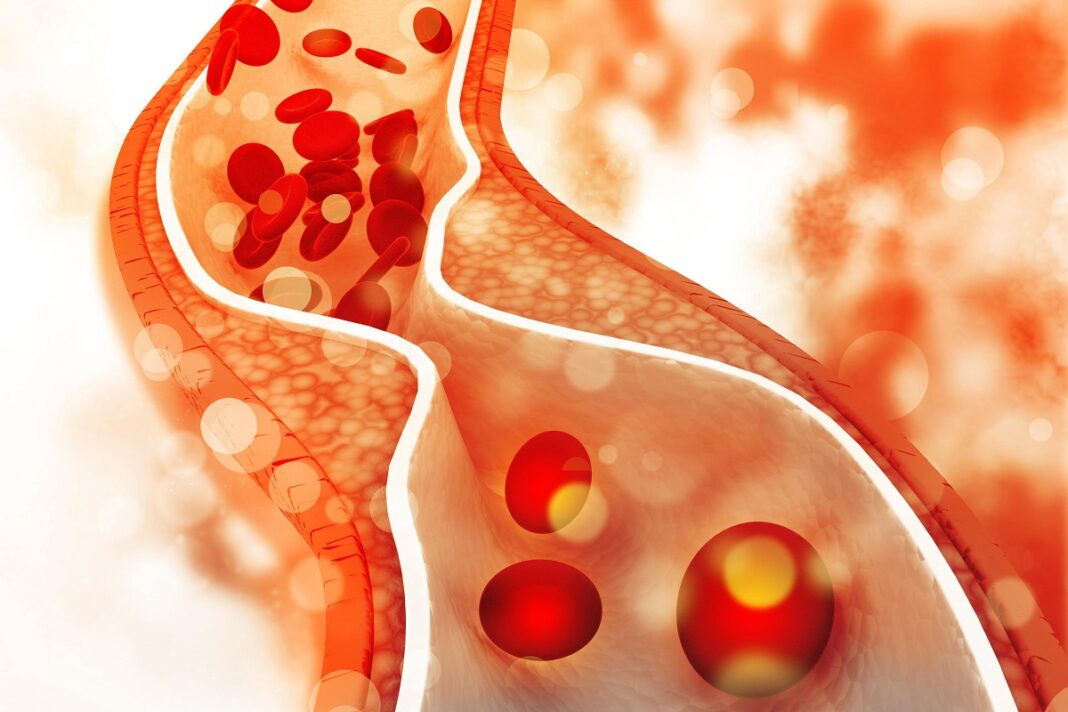

Αναμφισβήτητα, η διατροφή επηρεάζει αύξηση αλλά και τη μείωση της χοληστερίνης. Τα τελευταία χρόνια, η αυξημένη τιμή της ολικής και κυρίως της «κακής» LDL-χοληστερόλης είναι πολύ συχνή. Κι όχι μόνο στους ηλικιωμένους. Οι γιατροί λοιπόν εστιάζουν στην αλλαγή του τρόπου ζωής αλλά κυρίως της διατροφής.

Συγκεκριμένα, συνιστούν μια χορτοφαγική κατά βάση διατροφή με έμφαση σε προϊόντα που βοηθούν στη μείωση της LDL .